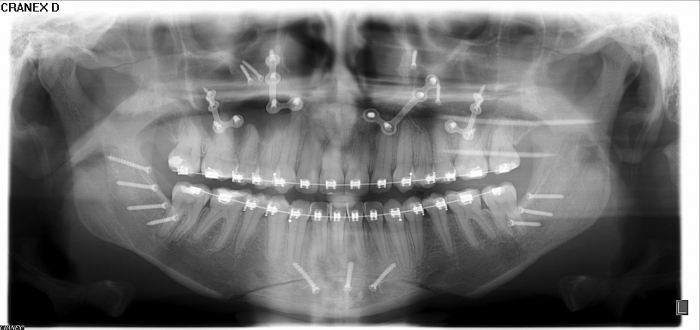

Rx panorâmico inicial

Rx panorâmico apos a cirurgia